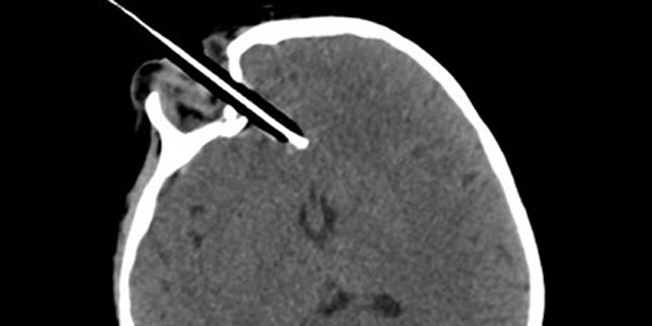

Dvogodišnja Wren Bowell iz Somerseta imala je nevjerojatnu sreću što je ostala živa kad joj se olovka zabila 4 centimetra u očnu duplju i za samo 1 milimetar promašila izuzetno važnu krvnu žilu. Da ju je oštetila, Wren bi vjerojatno umrla, a sigurno bi zadobila teška oštećenja mozga.

Olovka joj se tako čvrsto zabila u lubanju da su joj neurokirurzi tijekom četverosatne operacije morali otkloniti dio lubanje kako bi ju izvadili. Taj su dio vratili natrag, pričvrstivši ga biorazradivim vijcima. Srećom, sve je prošlo bez ikakvih posljedica i djevojčica se u potpunosti oporavila. Pravo je čudo, naglasili su liječnici, da joj čak niti očna jabučica nije stradala.